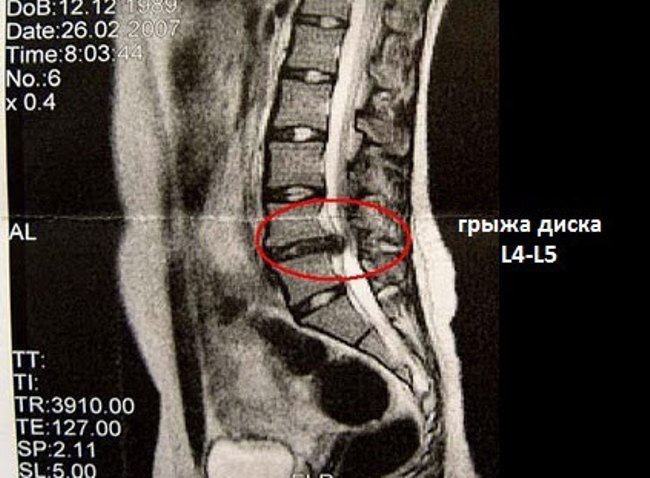

В диагнозе обязательно отражается, какой именно диск поражен грыжей. Для его обозначения используют специальную буквенно-цифровую систему.

Диск l4l5 отделяет 4 и 5 позвонок поясничного отдела (он обозначается латинской буквой l)

Аналогично диск л1л2 отделяет 1 и 2 позвонки поясницы, а l5s1 – 5 позвонок поясницы и 1 позвонок копчикового отдела. Есть свои обозначения и для позвонков шейного отдела – например, с5с6 отделяет 5 и 6 позвонки шеи. Однако там грыжа наблюдается реже всего ввиду небольшой нагрузки на шею, по сравнению с поясницей.